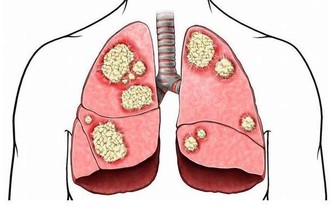

有前列腺炎的快行動起來,不花錢,自救下半身!濕熱壅滯引起的前列腺炎,前列腺炎屬於中醫「精濁」、「勞淋」、「白淫」的範疇。濕熱壅滯、陰虛火動、腎虛陽衰、氣血瘀滯均可致本病,其中以濕熱壅滯最為常見,表現為小便頻急、尿道熱痛、尿末時有白濁從尿道滴出,小腹、腰骶、會陰、睪丸脹痛不適,口乾苦而黏等。